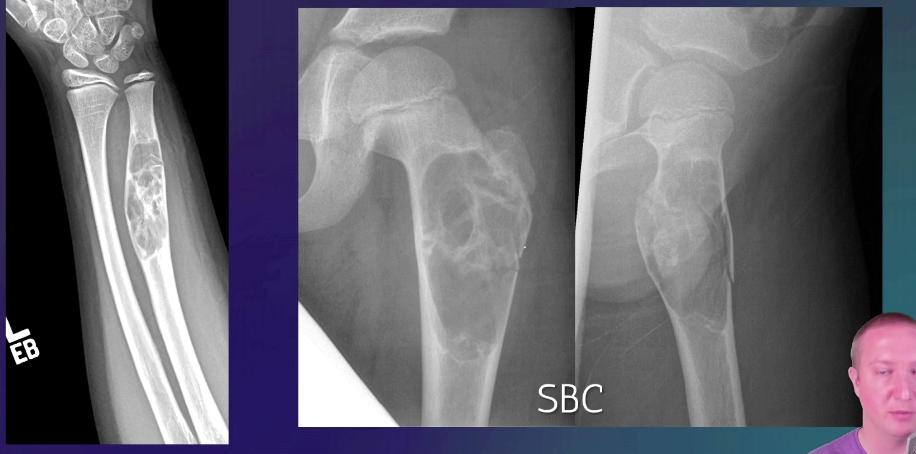

NAME 3 central bone lesions and 4 eccentric bone tumours

• Central

• Simple Bone Cyst

• Fibrous displasia

• Enchondroma

• Eccentric

• Giant Cell Tumour

• FOD/NOF

• CMF (chondromyxoid fibroma)

• Osteoma